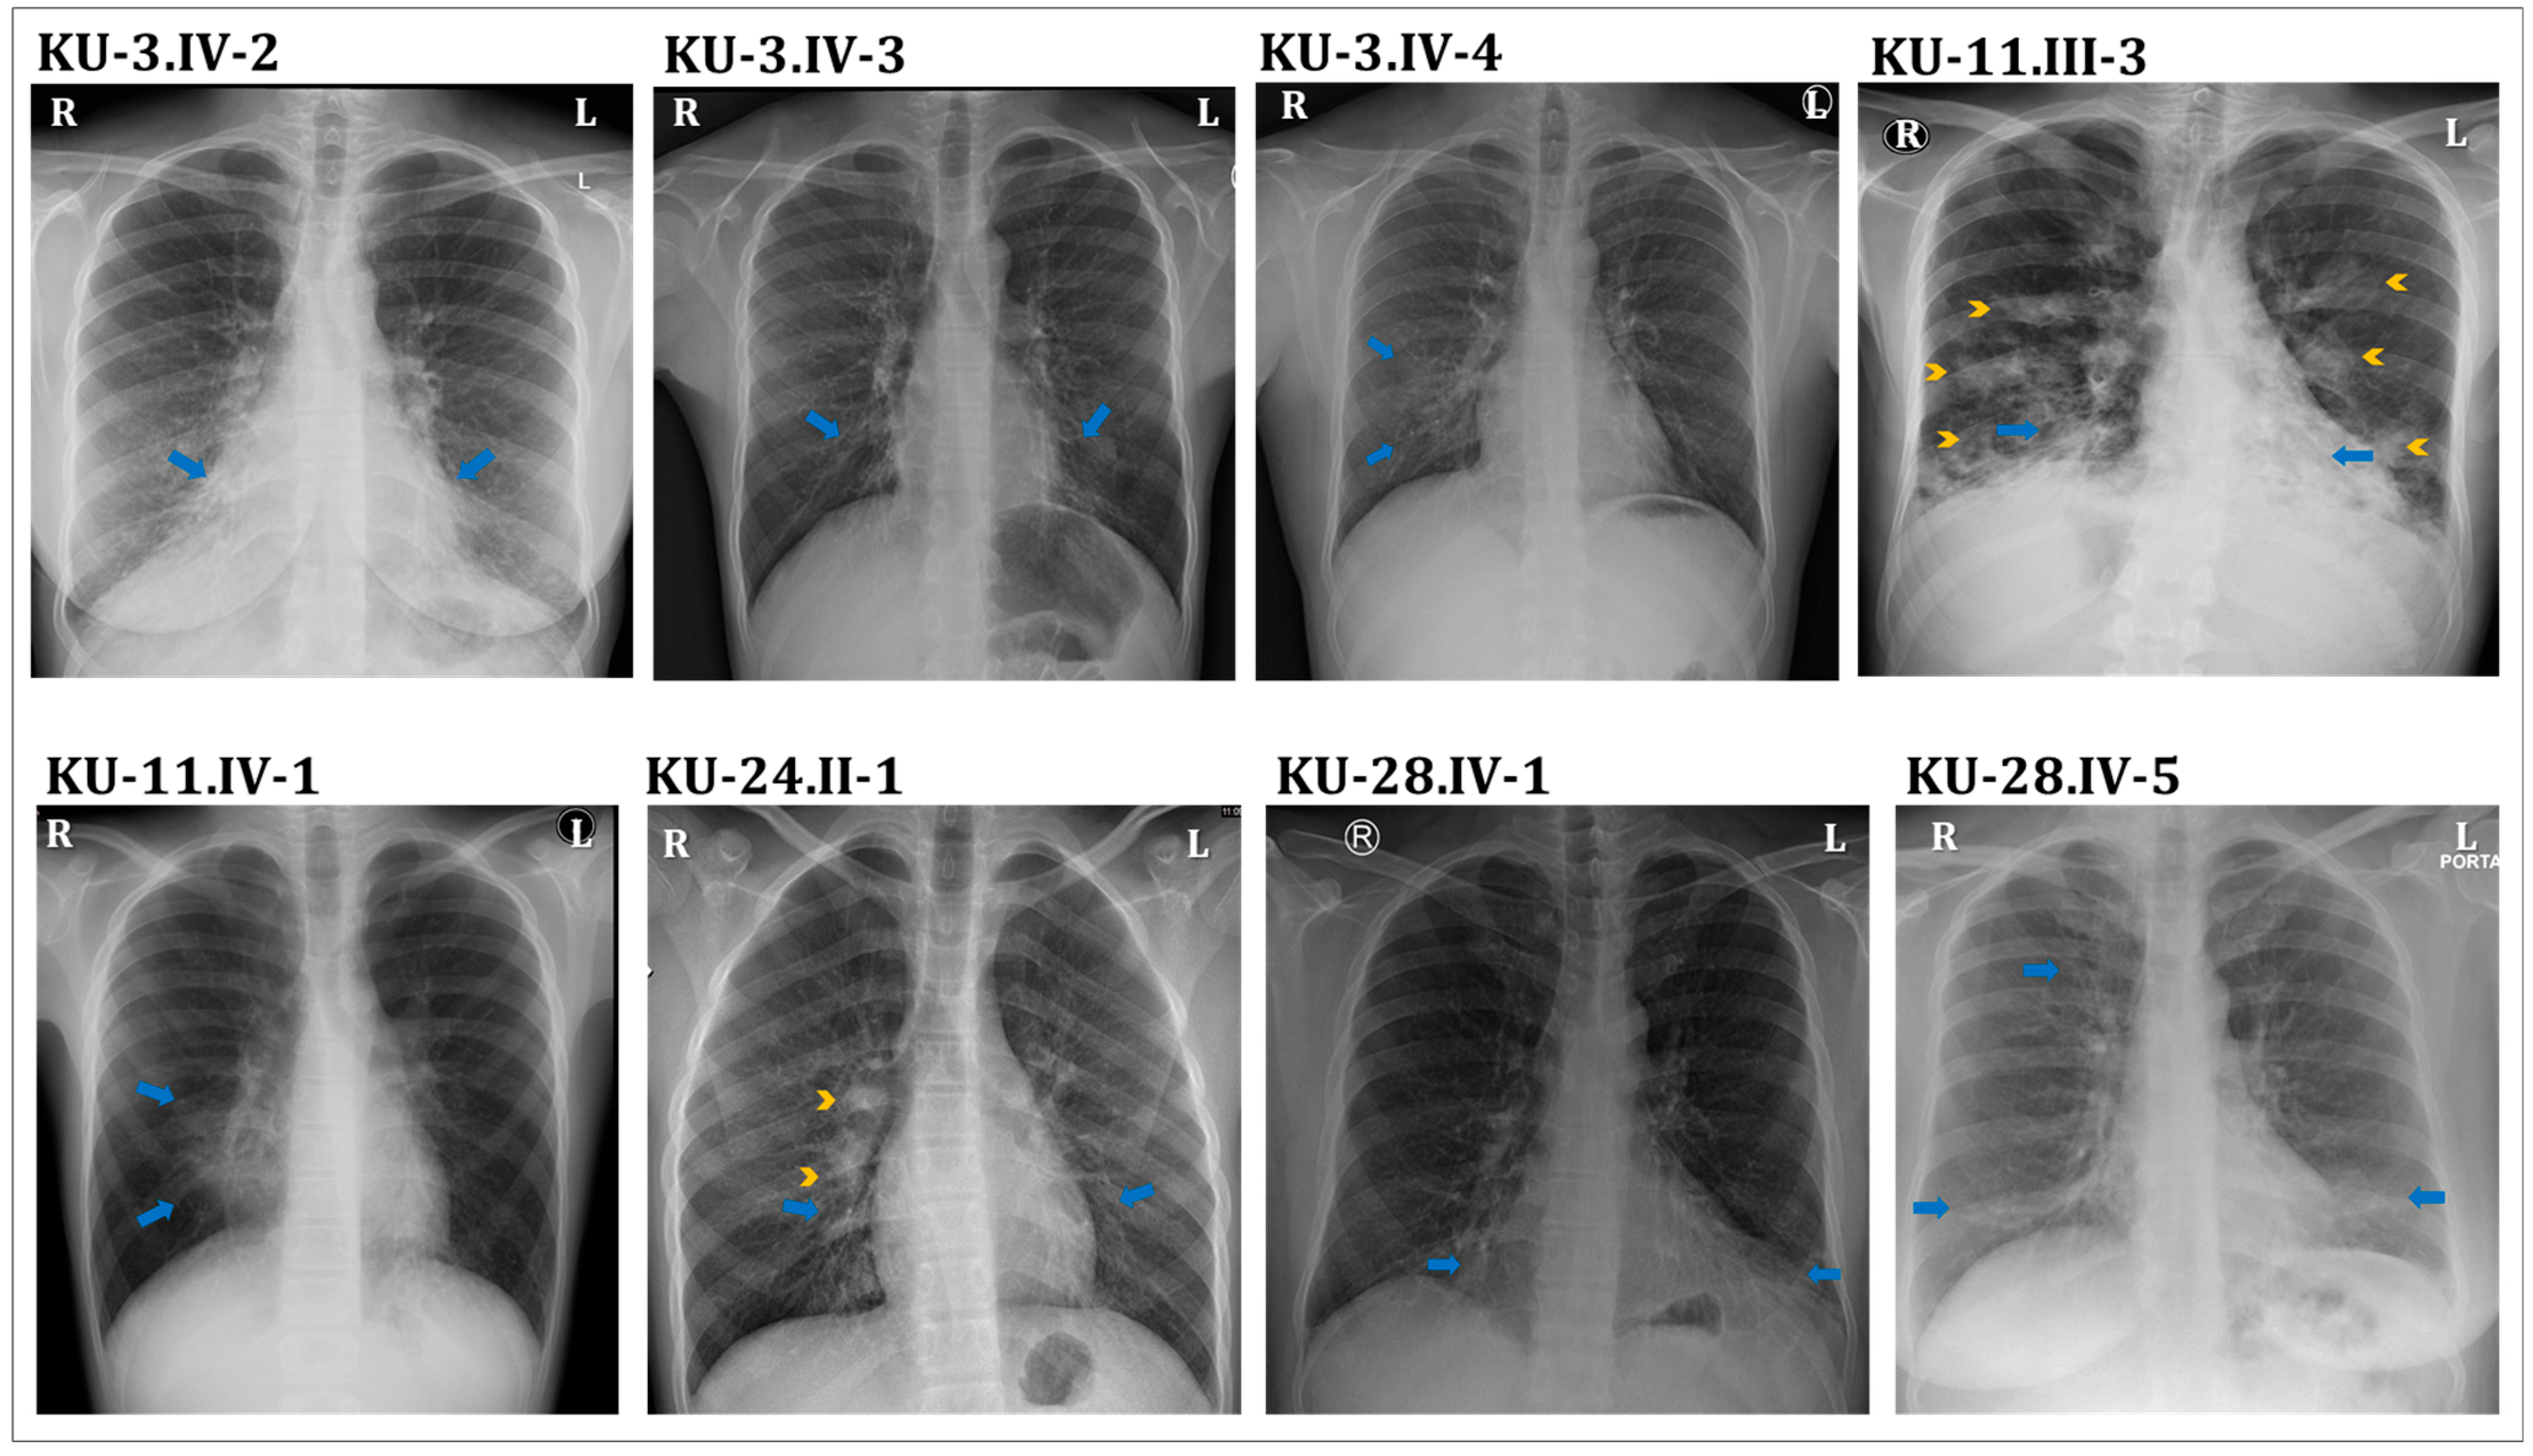

3.3. Detection of Ultrastructural Defects of the Cilia